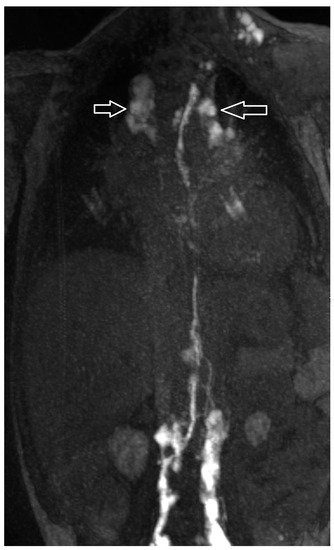

| 1 | 4 | increased signal neck, mediastinum, hilum, perihilar, interstitial lung parenchyma, pleural effusion | abnormal, perfusion to the lung, intercostal flow, dilated lymphatic networks in neck, mediastinum, hilum and perihilar | in the right apical lung | diuretics, sildenafil, non-invasive ventilatory support | lymphatic intervention | Resolution of CT (FU: 10 m, cessation of ventilatory support. |